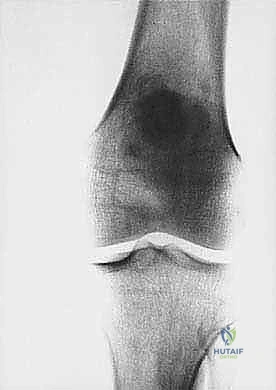

* الساركوما العظمية (Osteosarcoma): الأكثر شيوعاً، تظهر عادة حول الركبة (أسفل الفخذ أو أعلى القصبة).

| حدود الورم في الأشعة | واضحة، محددة بدقة (Sclerotic margin) | غير واضحة، متآكلة (Moth-eaten appearance) |

| اختراق قشرة العظم | نادر جداً | شائع جداً، يمتد للأنسجة الرخوة المحيطة |

تحديد مراحل الورم (Staging): نظام Enneking

تحديد مرحلة الورم هو الخطوة الأهم قبل أي تدخل جراحي. يعتمد الدكتور هطيف على نظام (Enneking) لتحديد مراحل أورام العظام، والذي يعتمد على ثلاثة عوامل:

2. الموقع (Site - T): هل الورم داخل الحيز العظمي (Intracompartmental - T1) أم اخترق القشرة وخرج للحيز الخارجي (Extracompartmental - T2)؟

مبادئ الاستئصال الجراحي: الهوامش الجراحية (Surgical Margins)

الهدف الأول في جراحة الساركوما ليس فقط إزالة الكتلة المرئية، بل استئصالها مع طبقة من الأنسجة السليمة المحيطة بها لضمان عدم ترك أي خلايا مجهرية. تُصنف الهوامش الجراحية إلى:

- الاستئصال الواسع (Wide Resection): وهو المعيار الذهبي. يتم استئصال الورم مع طبقة من الأنسجة السليمة المحيطة به (العضلات، العظام). هذا ما يبرع فيه الدكتور هطيف لضمان الشفاء التام.